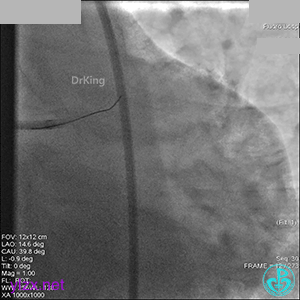

右冠脉血流3级,患者无症状,终止手术。

术后患者无特殊不适。

1周后再次上台,右冠脉3级血流,3段局限性严重狭窄,内膜模糊,应该是上次操作夹层遗留下的血肿。